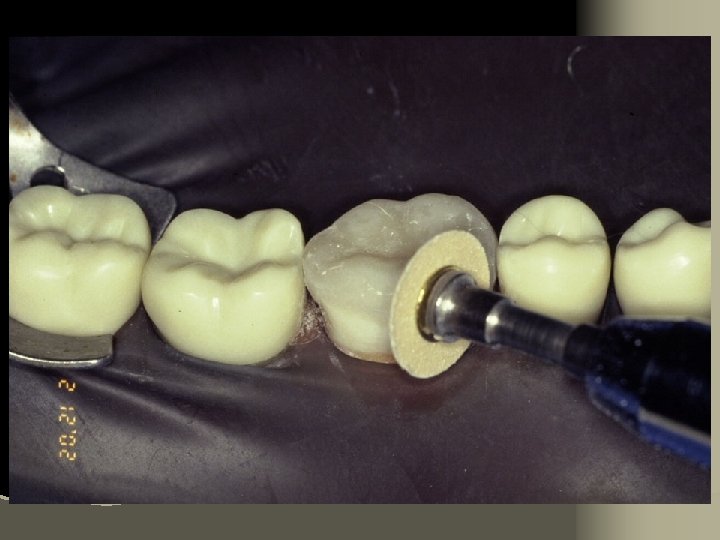

11. Place matrix to protect adjacent teeth from etchant 12. Etch prepared tooth surfaces (phosphoric acid). Rinse and lightly air dry 13. Apply prime/bond for 15 seconds 14. Air thin for 3 seconds – AVOID POOLING 15. Light cure for 20 seconds per surface

Conventional composite finishing techniques